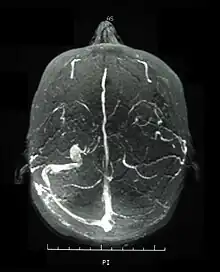

Funduscopic photo left eye centered on the optic disc

Visual acuity, or color vision loss with concurrent mucocutaneous lesions or systemic Behçet's disease symptoms should raise suspicion of optic nerve involvement in Behçet's disease and prompt a work-up for Behçet's disease if not previously diagnosed in addition to an ocular work-up. Diagnosis of Behçet's disease is based on clinical findings including oral and genital ulcers, skin lesions such as erythema nodosum, acne, or folliculitis, ocular inflammatory findings and a pathergy reaction. Inflammatory markers such ESR, and CRP may be elevated. A complete ophthalmic examination may include a slit lamp examination, optical coherence tomography to detect nerve loss, visual field examinations, fundoscopic examination to assess optic disc atrophy and retinal disease, fundoscopic angiography, and visual evoked potentials, which may demonstrate increased latency. Optic nerve enhancement may be identified on Magnetic Resonance Imaging (MRI) in some patients with acute optic neuropathy. However, a normal study does not rule out optic neuropathy. Cerebrospinal fluid (CSF) analysis may demonstrate elevated protein level with or without pleocytosis. Imaging including angiography may be indicated to identify dural venous sinus thrombosis as a cause of intracranial hypertension and optic atrophy.

In an epidemiologic study, 56 percent of patients with Behçet's disease developed ocular involvement at a mean age of 30.[45] Ocular involvement was the first manifestation of Behçet's disease in 8.6 percent of patients.[45] Ocular Behçet's disease with involvement of the optic nerve is rarely reported. Among patients with ocular Behçet's disease funduscopic findings of optic atrophy, and optic disc paleness have been identified with a frequency of 17.9 percent and 7.4 percent, respectively. Other fundoscopic findings include vascular sheathing (23.7%),[7] retinal hemorrhage (9%),[7] macular edema (11.3%),[7] branch retinal vein occlusion (5.8%),[7] and retinal edema (6.6%).[7] However, optic atrophy was the most significant cause of visual impairment identified in 54 percent of patients with ocular Behçet's disease and permanent visual impairment.[7]